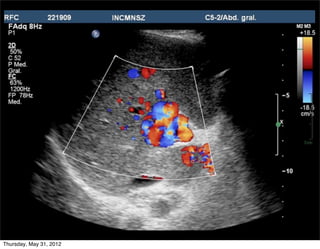

Flujo hepatofugo

• Definición: Flujo que se ALEJA del hígado

Importante en:

1. Diagnóstico HP

2. Conocer permeabilidad de

shunt portosistémico

3. Px hepatópatas

4. Seleccionar pacientes NO

candidatos a

• Quimioembolización

intraarterial

• Portografía arterial por

TC

incich/grupo ct scanner                       Departamento de Radiología/Unidad PET-CT

SIEMPRE demostrar en la misma

• Portografía arterial por   imagen el flujo petal de la arteria

TC                               con el fugo portal